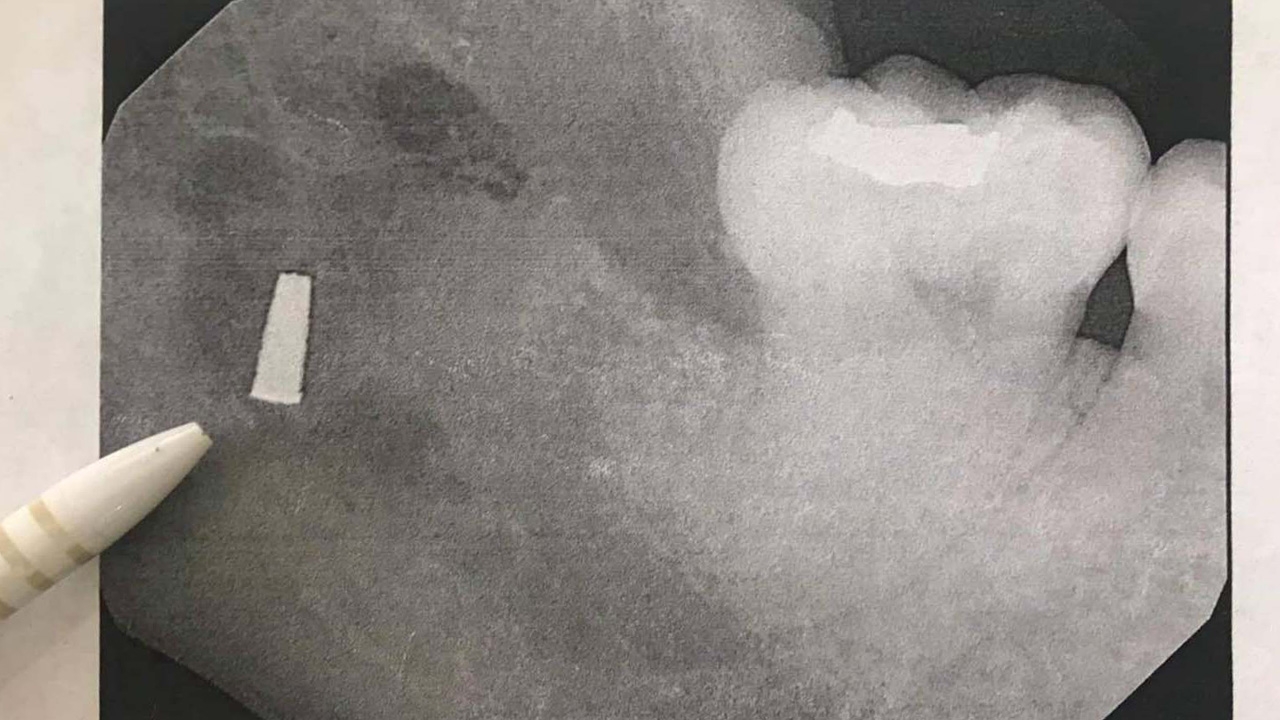

นางกฤติกา เปิดเผยว่า ย้อนไปเมื่อปี 2558 แพทย์โรงพยาบาลแห่งหนึ่งใน จ.นราธิวาส ได้ทำการผ่าตัดรักษาอาการฟันคุด แล้วลืมหัวกรอฟันไว้ในเหงือก กระทั่งเมื่อปีที่แล้วแพทย์ทันตแพทย์ศาสตร์ มข. ได้ตรวจ และทำการผ่าตัดนำหัวกรอฟันออกมาได้ แต่ก็ต้องมีการนัดติดตามอาการทุกๆ 6 เดือน